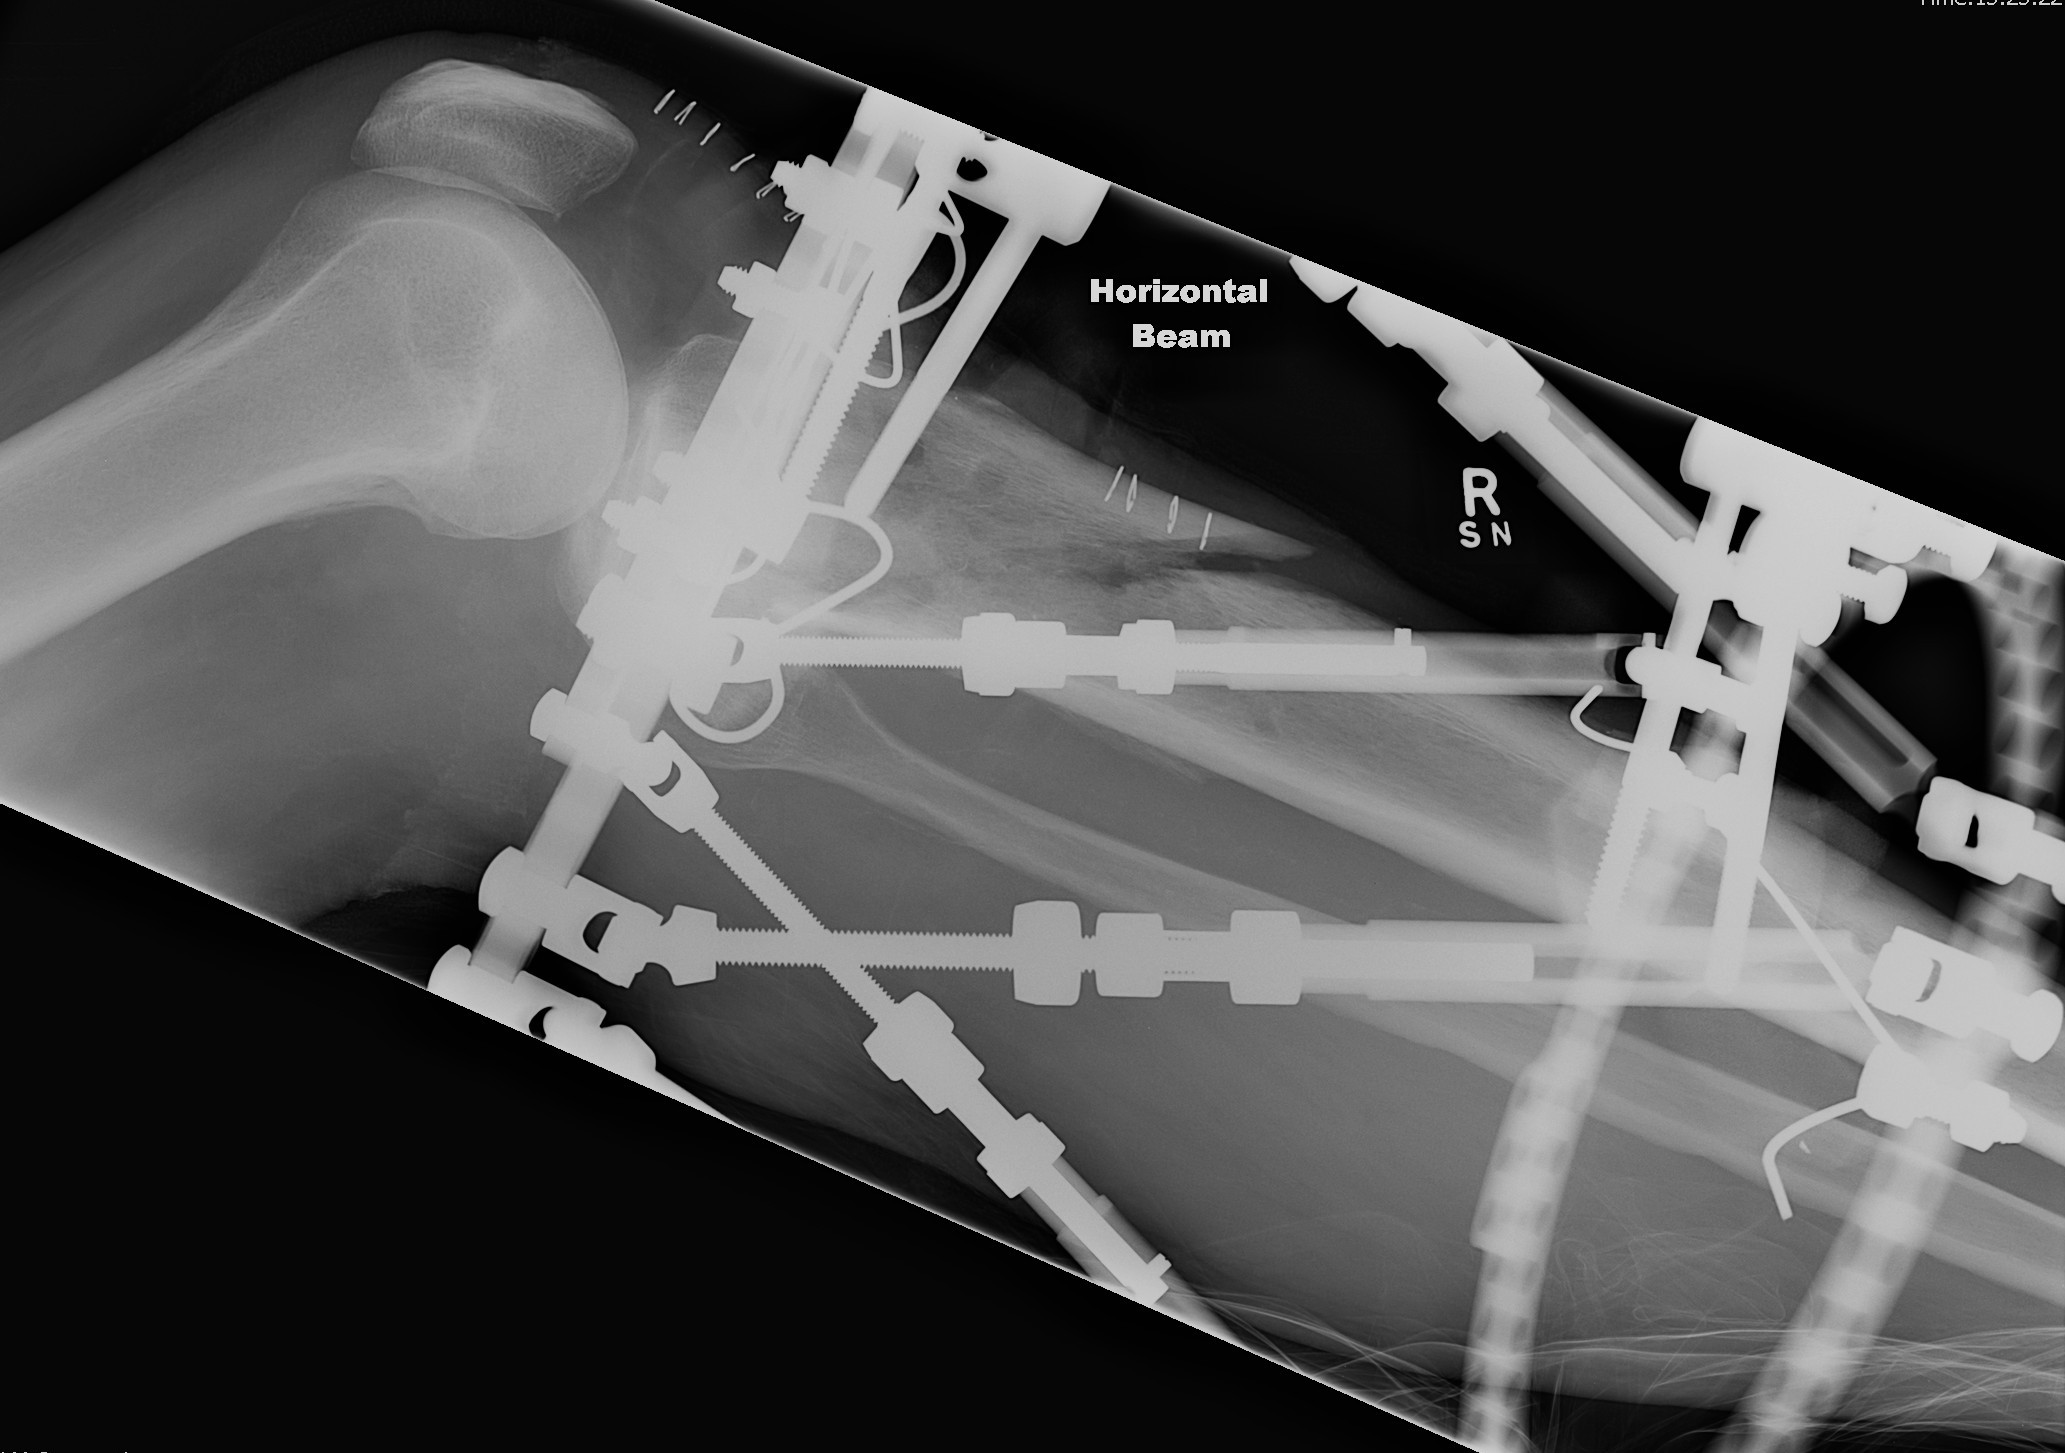

Xray of entire tibia and rings

- xray centred on proximal tab of proximal ring

- AP and Lateral all in one film

- the entire diameter of the rings must be on the film